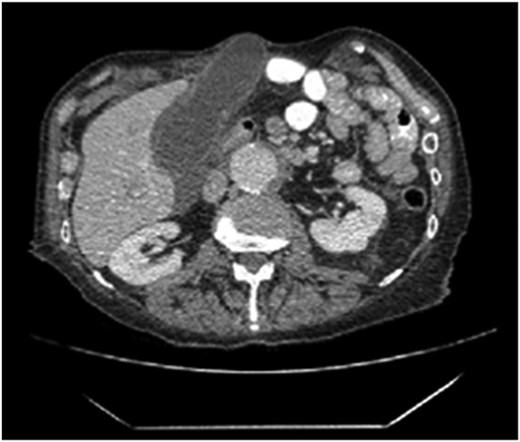

Seventy-six-year-old male with a past medical history of COPD and esophageal cancer status post gastric pull-through procedure 25 years prior, presented to the Emergency Department with a chief complaint of sudden onset epigastric pain that began 24 hours prior while at rest. The pain progressively worsened and radiated to both his right upper quadrant and back with associated chills and nausea/vomiting. He was found to be febrile (38.1C) with a leukocytosis (18.77), hyperbilirubinemia (2.8), transaminitis (418/196) and elevated alkaline phosphatase (168) and lipase (>2250). A CT abdomen/pelvis with IV contrast demonstrated a thickened gallbladder wall, pericholecystic fluid and associated edema of the pancreas consistent with acute cholecystitis and pancreatitis. While the CT showed postoperative changes given his history of esophagectomy with gastric conduit, multiple unique anatomic abnormalities were also noted, including the presence of the gallbladder through a ventral hernia to where it was flush with the skin/subcutaneous tissue of the anterior abdomen (Figs 1 and 2). By hospital day 2, the patient’s lab values were downtrending, consistent with a transient common bile duct stone. Follow-up MRCP confirmed the diagnosis of acute calculous cholecystitis with obstruction of the cystic duct and patency of the common bile and pancreatic ducts. The decision was made to take the patient to the operating room for cholecystectomy with cholangiography. In the operating room, a right subcostal incision was made using electrocautery with a hernia sac encountered directly deep to the subcutaneous tissue. The peritoneum of the hernia was opened and the tip of the gallbladder was immediately encountered. On gross examination, necrosis was noted with evidence of microperforation into the hepatic plate, though no gross contamination was present. The gallbladder was dissected off the hepatic plate, the cystic artery was identified and ligated and stones palpable within the cystic duct were milked retrograde prior to ligation of the cystic duct. The gallbladder was removed and sent for definitive pathologic review. The hernia sac and skin were reapproximated in a multi-layered closure but the fascial edges were not amenable to primary closure secondary to both chronicity and size of the incisional hernia. The patient tolerated the procedure well and was able to discharge home on hospital day 5 (Post-operative day 3). Final pathology was consistent with acute calculous gangrenous cholecystitis. The patient was seen for follow-up 1 month post-operatively and was doing well with no complaints or return of symptoms.

The coronal section of the abdomen/pelvis CT scan illustrating our patient’s incisional hernia containing his gallbladder.